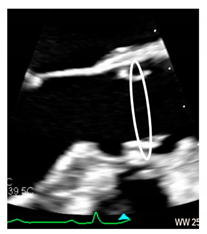

| Aortic annulus | The aortic annulus is the three-dimensional line that follows the hinge line of the leaflets on the aortic wall. This line of dense connective tissue has a crown-shaped appearance (white dotted line). | ![]() |